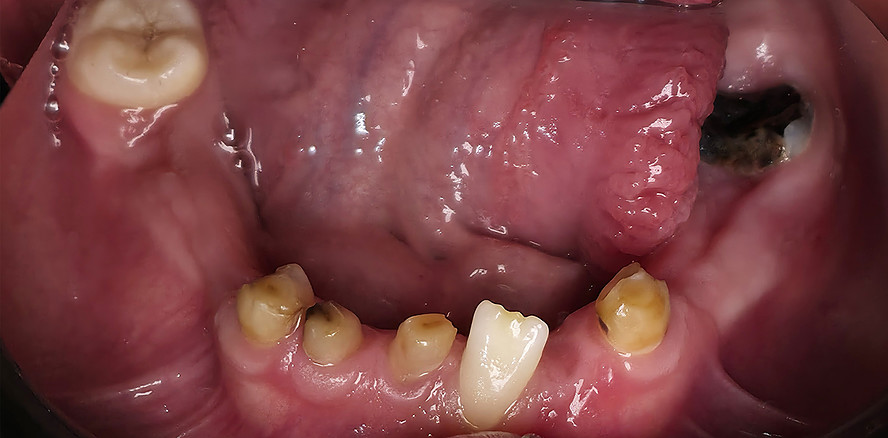

Der vorliegende Beitrag entstand aus einer kollegialen Anfrage: Eine 17-jährige Patientin mit ausgeprägten dentalen Auffälligkeiten wurde zur kieferorthopädischen Beratung überwiesen (Abb. 1a–c). Trotz zahlreicher vorangegangener zahnärztlicher Behandlungen war bis zu diesem Zeitpunkt keine syndromale Diagnose gestellt worden. Erst durch die sorgfältige Erhebung der allgemeinen und zahnmedizinischen Anamnese, die klinische Untersuchung sowie die gezielte Auswertung der dreidimensionalen Bildgebung ließ sich ein charakteristisches Muster erkennen. Auf dieser Grundlage ergab sich aus kieferorthopädischer Sicht der begründete Verdacht auf eine cleidokraniale Dysplasie, der die Vielzahl der dentalen, skelettalen und fazialen Befunde erstmals in einen schlüssigen klinischen Zusammenhang stellte.

Im vorliegenden Fall erfolgte die Überweisung durch eine zahnärztliche Kollegin mit der Bitte um kieferorthopädische Einschätzung des weiteren Vorgehens angesichts multipler nicht durchgebrochener Zähne, persistierender Milchzähne und zahlreicher überzähliger Zahnkeime.1

Das dentale Erscheinungsbild ist häufig sehr charakteristisch und erlaubt bereits früh einen Syndromverdacht. Typische Befunde sind:

• lang anhaltende Persistenz der Milchzähne

• ausgeprägte Retention der bleibenden Zähne

• multiple überzählige Zähne

• fehlende oder stark verzögerte spontane Zahndurchbrüche

• Engstände und Fehlstellungen